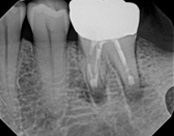

This person had root canal therapy many years ago. One root had excess material outside of the root preventing healing. Another root had a perforation (a hole) and a crack. The large root had a post and had not healed from the initial root canal treatment.

The post was removed, that root was retreated. The root with the excess material, an apicoectomy was done, the excess material, and infection cleaned out. The root with the perforation and crack was removed. The tooth healed and is still in function. This area is a poor area for an implant.